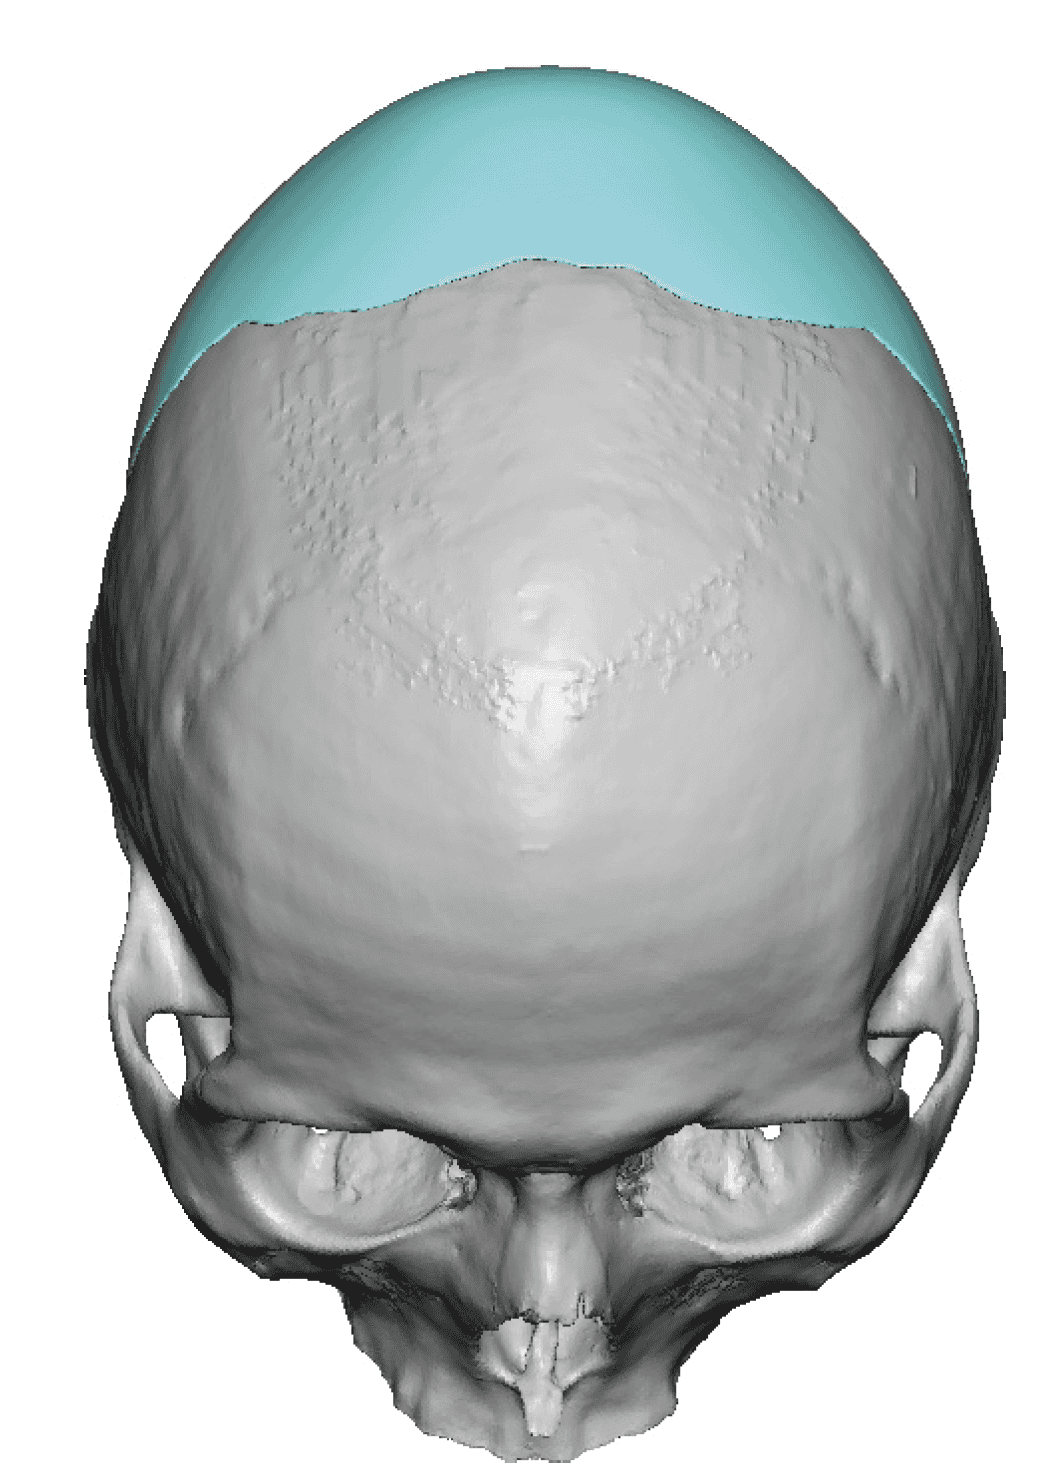

Patient 28

Desire for rounder shape to the top of the head from a congenital parasagittal deficiency skull shape.

Custom skull implant designed to fill in the parasagittal deficiencies.

Desire for rounder shape to the top of the head from a congenital parasagittal deficiency skull shape.

Custom skull implant designed to fill in the parasagittal deficiencies.